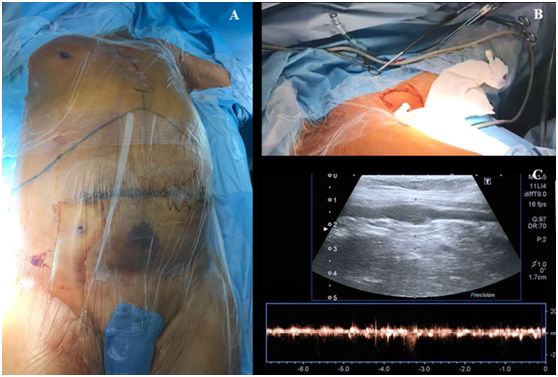

操作前,将患者置于平躺仰卧位,头部自然居中位,左上肢掌心向上外展90度(图1,A)。超声探头上涂上耦合剂,用无菌保护套包裹超声探头及导线。

从上臂近端至腋窝处超声预扫描,同时探查腋动脉和腋静脉的长轴平面(图1,BC),关注用最小的压力来控制超声探头,避免把血管压瘪。然后用多普勒和/或彩色血流来评估静脉及动脉的通畅性。

图1,A肝移植术患者体位,B-C腋静脉超声预扫描。